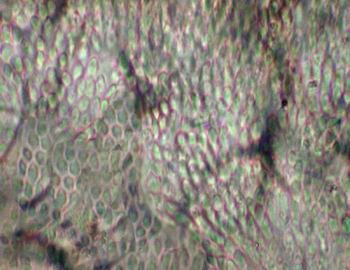

Visión específica: el esmalte está constituido por los prismas mineralizados del esmalte; por ello puede verse, según el corte, a nivel de su diámetro mayor o del menor, en este último caso ofreciendo la imagen clásica en ojo de cerradura. Ocupan todo el espesor del esmalte, desde la unión amelodentinaria a la superficie libre. Por este motivo son más largos los de la zona oclusal que los que se sitúan en la cervical. Por debajo de la unión amelodentinaria y hacia la zona pulpar vemos otra estructura mineralizada, la matriz dentinaria. En este caso, está también surcada de profundidad a superficie por unos túbulos dentinarios en los que se alojan las prolongaciones de los odontoblastos en el diente vital. En el centro de la pieza dentaria, a nivel de la cámara, observamos un material desestructurado que se corresponde con el tejido pulpar, que con este tipo de procesado no se conserva adecuadamente para su estudio pormenorizado.

Visión específica: el esmalte aparece constituido por unidades de material inorgánico, de morfología alargada, a modo de varillas que se conocen como los prismas del esmalte. Se dirigen desde la unión amelodentinaria a la superficie libre, siguiendo un recorrido serpenteante. La dentina, inmediatamente por debajo, se observa como una matriz mineralizada surcada por los túbulos dentinarios en forma de S itálica cuando son seccionados longitudinalmente, o como pequeños estructuras esféricas al corte transversal. En su interior se observan restos de la prolongación de los odontoblastos (con este tipo de procesado). La unión amelodentinaria presenta diferentes accidentes como penachos, laminillas y husos. El cemento acelular en la región superior y superficial de la raíz se distingue del cemento celular, ya que este último alberga, en el interior de la matriz mineralizada, a los cementocitos.